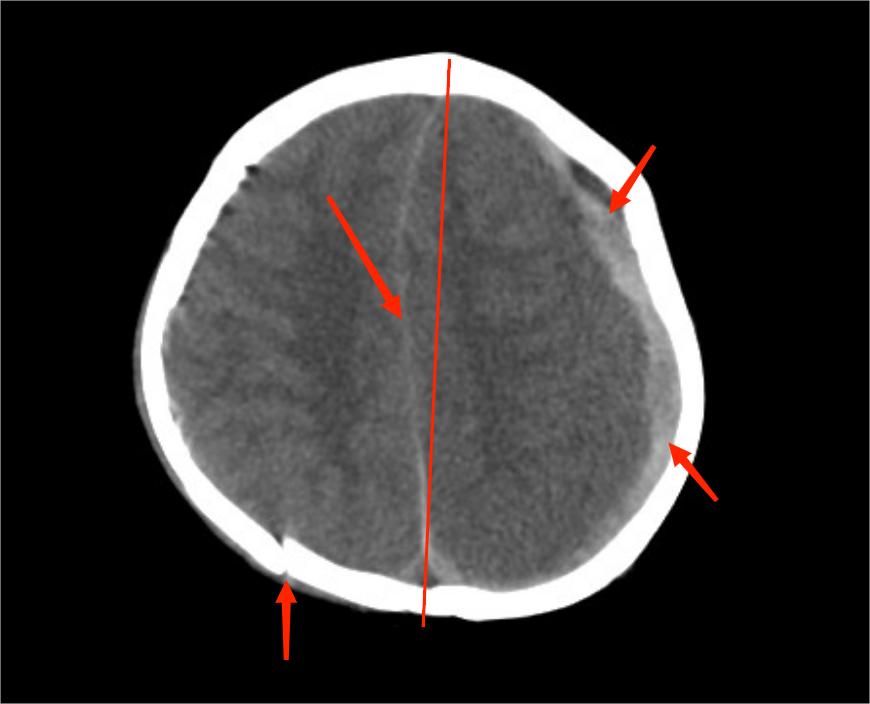

在急诊抢救室,医生发现小尹“双侧瞳孔不等大,对光反射消失”,结合昨天下午她有“摔伤后脑勺”病史,医生判应该“急性颅内出血所致脑疝可能”,紧急查头颅CT提示“硬膜下血肿可能,大脑镰下疝、左侧颞叶钩回疝可能,大脑镰、小脑幕密度增高,蛛网膜下腔出血,枕骨、顶骨骨折,头皮软组织稍肿胀”,考虑“考虑创伤性脑疝”。